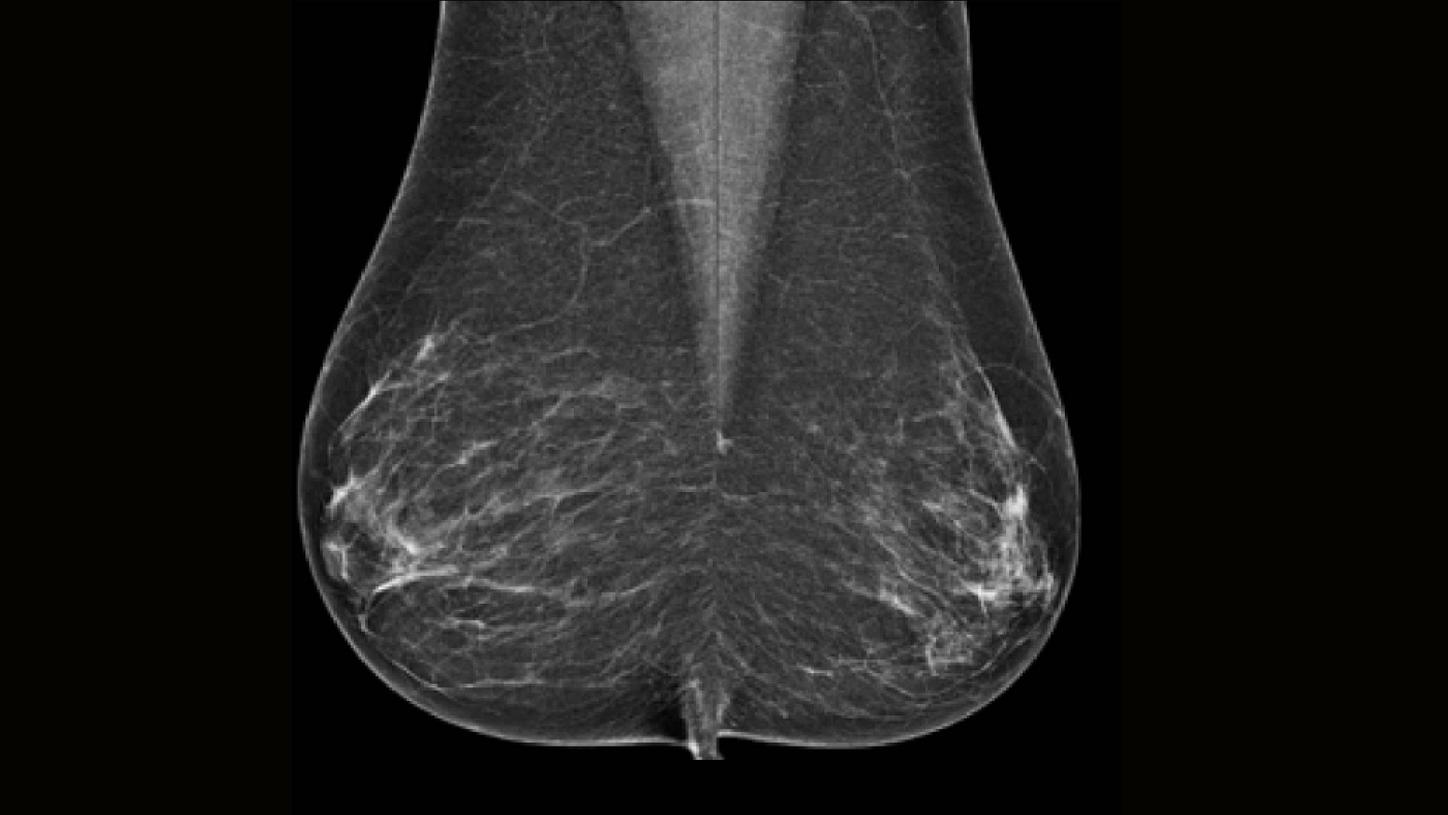

Paciente de 62 años que se presenta para mamografía de tamizaje. Luego de la mamografía se hace un rellamado de la paciente por una masa palpable localizada en el cuadrante externo del seno derecho. La paciente no tiene familiares con historial de cáncer de seno y presenta una densidad mamaria BI-RADS B.